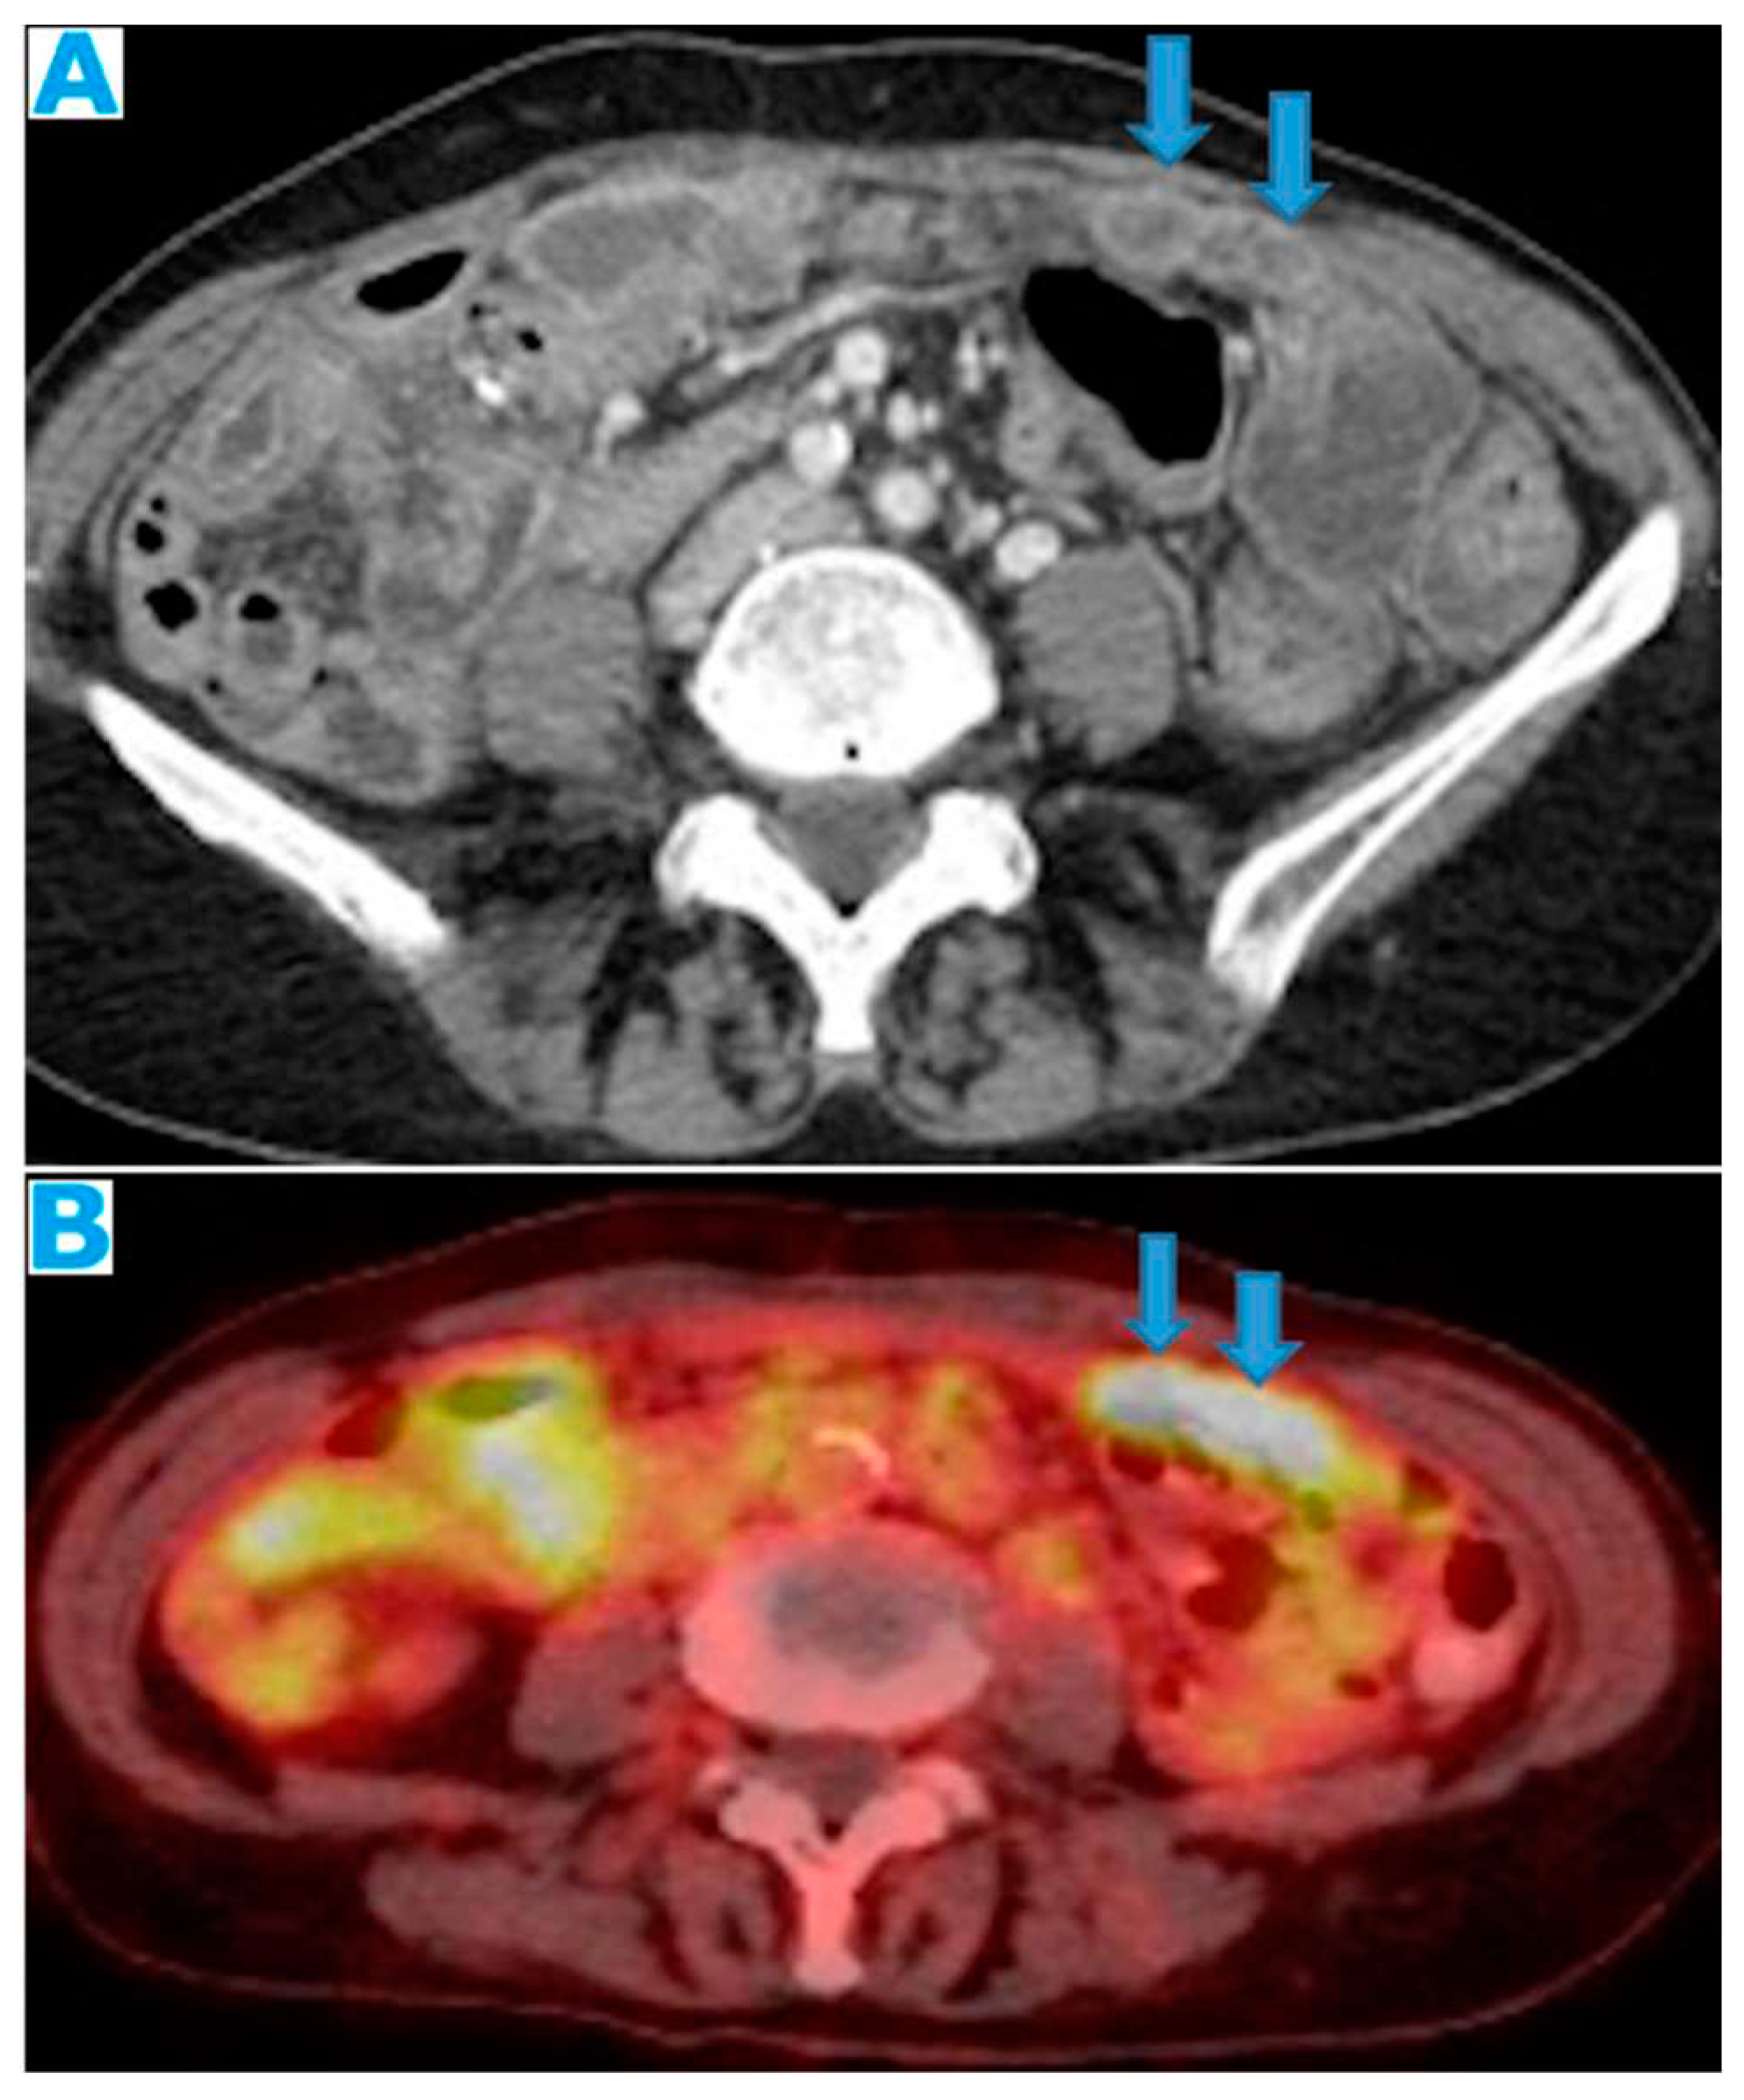

Figure 20.

Axial CE CT (A), FDG PET CT (B). PC from colon adenocarcinoma: Nodular deposits within the omentum that were originally mistaken for SB loops on CT, due to scarce intrabdominal fat.